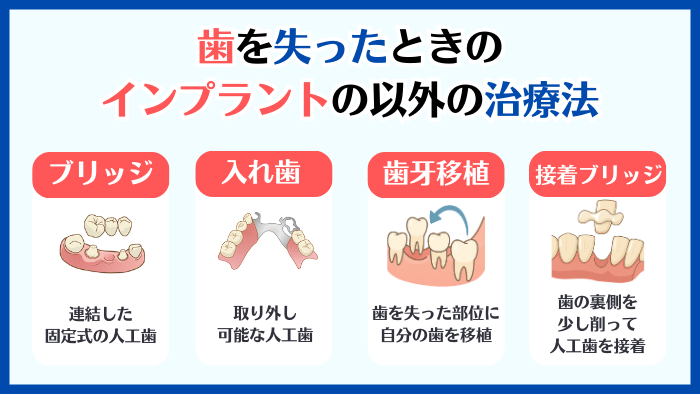

4:インプラント以外の治療法の紹介と比較

歯を失った場合の治療法は、インプラントだけではありません。

インプラントが絶対ダメなのかどうかを判断する際には、必ずインプラント以外の治療法についての理解も深めるようにしましょう。

ここでは、インプラント以外の治療法である

- ブリッジ

- 入れ歯

- 歯牙移植

- 接着ブリッジ

について、それぞれのメリット・デメリットを簡単に解説し、どのような場合に適しているかをご紹介します。

4-1:ブリッジ

ブリッジとは、失った歯の両隣にある健康な歯を土台にして、連結した固定式の人工歯を取り付ける治療法です。

1本または数本の歯を失い、その両隣の歯が健康な場合に適した治療になります。

4-3:歯牙移植

歯牙移植とは、噛み合わせと関係のない健康な歯を、歯を失った部分に移植する治療法です。

可能であれば40歳以下で、健康かつ噛み合わせに関係のない移植できる歯がある方に適しています。

4-4:接着ブリッジ

接着ブリッジとは、両隣の健康な歯の裏側を少し削って人工歯を接着させ、歯がない部分を補う治療法のことです。

歯ぎしりや食いしばりの習慣がなく、前歯など噛み合わせの力がかかりにくい歯を1本失った方に適しています。

▼インプラント以外の治療法

- ブリッジ

- 入れ歯

- 歯牙移植

- 接着ブリッジ